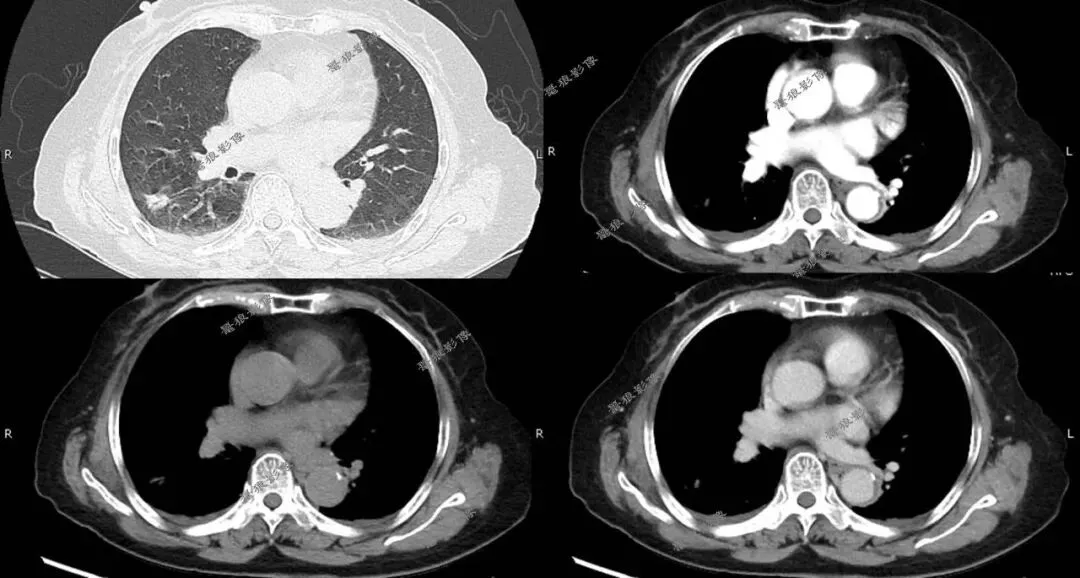

二、后行胸部CT平扫+增强(如下图):

胸部CT平扫+增强提示:

右肺下叶背段(IM118)见一浅分叶状实性结节,大小约为17mm×14mm,病灶边缘可见多发短毛刺,邻近斜裂稍凹陷,增强扫描病灶呈较明显不均匀强化。左前上纵隔见一类圆形软组织肿块,边界尚清,大小约69mm×44mm×51mm,密度较均匀,增强扫描病灶呈较均匀性轻度强化。

1.右肺下叶背段浅分叶状实性结节,考虑肺Ca可能性大,建议治疗后复查。

2.左前上纵隔软组织肿块,考虑胸腺瘤,必要时进一步检查以除外其它肿瘤性病变。